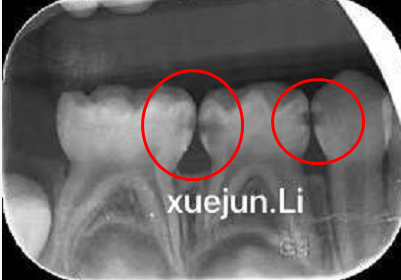

更可怕的是,邻面龋这个得天独厚的地理优势,给检查和治疗都增加了难度。为了揪出邻面龋,医生通常会先用专业检查工具轻轻试探一下,要是角度问题不利于探诊检查,就需要给牙齿拍个牙片了。

图片

看看这个案例,也是牙面外观完整,看不出大问题,实际上缝隙之间的隐匿龋坏很严重了,一拍片子全都“现形”了